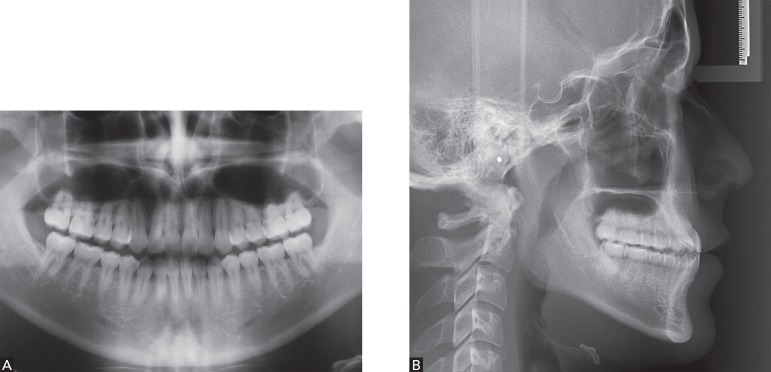

A panamoramic radiograph confirmed the presence of all permanent teeth, with third molars in occlusion and a periodontal condition that was consistent with patient's age. Tooth #14 had a provisional crown as well as an intracanal post and presented favorable conditions for orthodontic treatment onset (Fig 3A).

Figure 3.

Initial photographs: A) Panoramic radiograph; B) Profile radiograph

From a skeletal standpoint, morphological evaluation of the cephalogram revealed a negative maxillomandibular step with mild mandibular prognathism, especially due to an anticlockwise mandibular rotation, given that the cephalogram was taken at maximal intercuspation. Although mandibular incisors were lingually tipped and strongly compensated, they were also well inserted into the symphysis. Conversely, maxillary incisors were well positioned in the maxillary bone (Fig 3B).